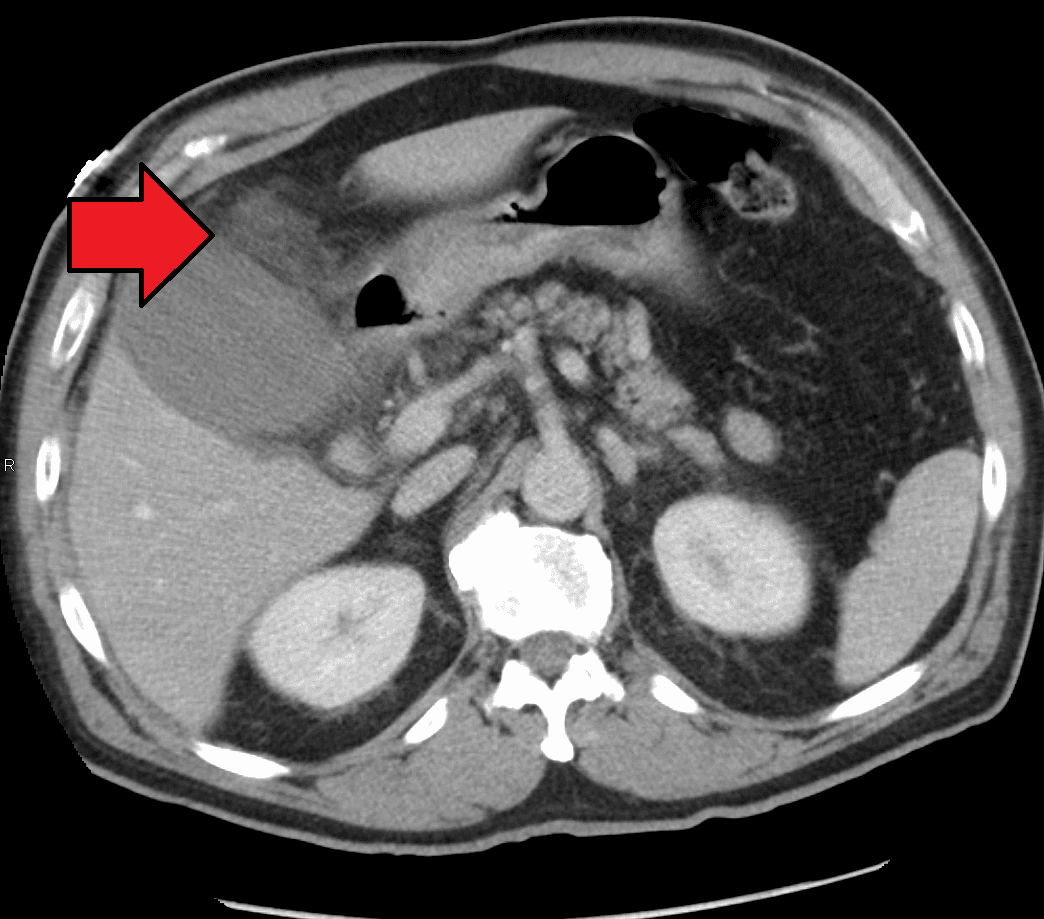

Cholecystitis is inflammation of the gallbladder. Symptoms include right upper abdominal pain, pain in the right shoulder, nausea, vomiting, and occasionally fever. Often gallbladder attacks (biliary colic) precede acute cholecystitis. The pain lasts longer in cholecystitis than in a typical gallbladder attack. Without appropriate treatment, recurrent episodes of cholecystitis are common. Complications of acute cholecystitis include gallstone pancreatitis, common bile duct stones, or inflammation of the common bile duct. More than 90% of the time acute cholecystitis is caused from blockage of the cystic duct by a gallstone. Risk factors for gallstones include birth control pills, pregnancy, a family history of gallstones, obesity, diabetes, liver disease, or rapid weight loss. Occasionally, acute cholecystitis occurs as a result of vasculitis or chemotherapy, or during recovery from major trauma or burns. Cholecystitis is suspected based on symptoms and laboratory testing. Abdominal ultrasound is then typically used to confirm the diagnosis. Treatment is usually with laparoscopic gallbladder removal, within 24 hours if possible. Taking pictures of the bile ducts during the surgery is recommended. The routine use of antibiotics is controversial. They are recommended if surgery cannot occur in a timely manner or if the case is complicated. Stones in the common bile duct can be removed before surgery by endoscopic retrograde cholangiopancreatography (ERCP) or during surgery. Complications from surgery are rare. In people unable to have surgery, gallbladder drainage may be tried. About 10–15% of adults in the developed world have gallstones. Women more commonly have stones than men and they occur more commonly after age 40. Certain ethnic groups are more often affected; for example, 48% of American Indians have gallstones. Of all people with stones, 1–4% have biliary colic each year. If untreated, about 20% of people with biliary colic develop acute cholecystitis. Once the gallbladder is removed outcomes are generally good.